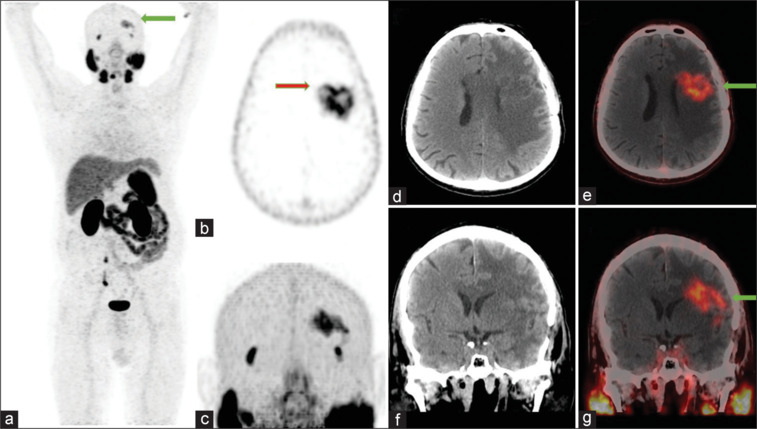

多形性胶质母细胞瘤(GBM)是一种高级别脑肿瘤,复发率高。我们报告一名57岁男性左额叶GBM患者于2023年6月接受手术和放疗,并因临床怀疑复发而转诊68Ga-PSMA 11 PET/CT。扫描显示左侧额叶病变有强烈的示踪剂摄取,伴有严重水肿,与复发相符。我们的病例强调了68Ga PSMA 11 PET/CT成像在可疑胶质母细胞瘤复发中的作用,这是PSMA治疗GBM的第一步。

Glioblastoma multiforme (GBM) is a high-grade brain tumor with a high recurrence rate. We present the case of a 57-year-old man with left frontal lobe GBM who was operated on and received radiation therapy in June 2023 and was referred for 68Ga-PSMA 11 PET/CT with a clinical suspicion of recurrence. The scan showed intense tracer uptake in the left frontal lobe lesion with severe edema, which was consistent with recurrence. Our case underscores the role of 68Ga PSMA 11 PET/CT imaging of suspected glioblastoma recurrence which is the initial step in GBM theranostics with PSMA.